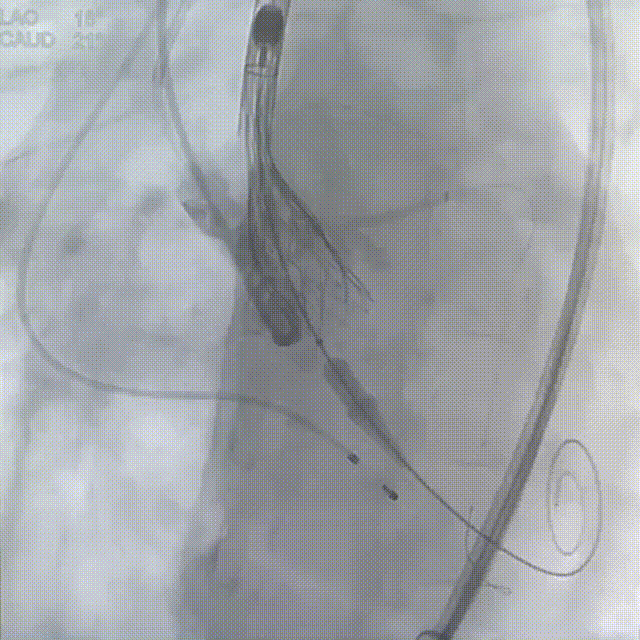

22mm球囊预扩

瓣膜定位

瓣膜释放至75%

瓣膜脱钩

瓣膜完全释放

22mm球囊后扩

完成植入

术后即刻超声显示:释放后瓣膜工作正常,患者的跨瓣压差由术前的83mm/Hg改善至术后的4mm/Hg,患者获益明显。